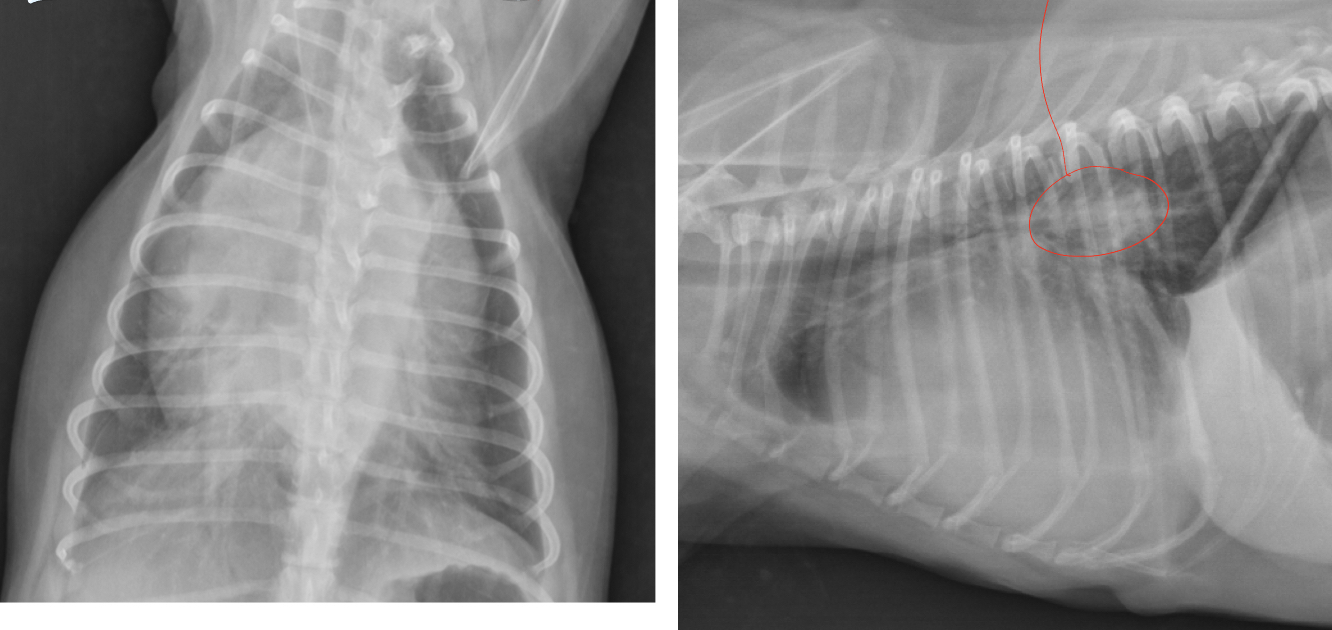

Q

puppy X-ray- what likely dx, identify 1-2

A

Dx: PDA (both artery and vein enlarged)

1. Artery

2. Vein

1 month old leonberger presented with distress and lethargy. What wrong

peritoneal-pericardial diaphragmatic hernia